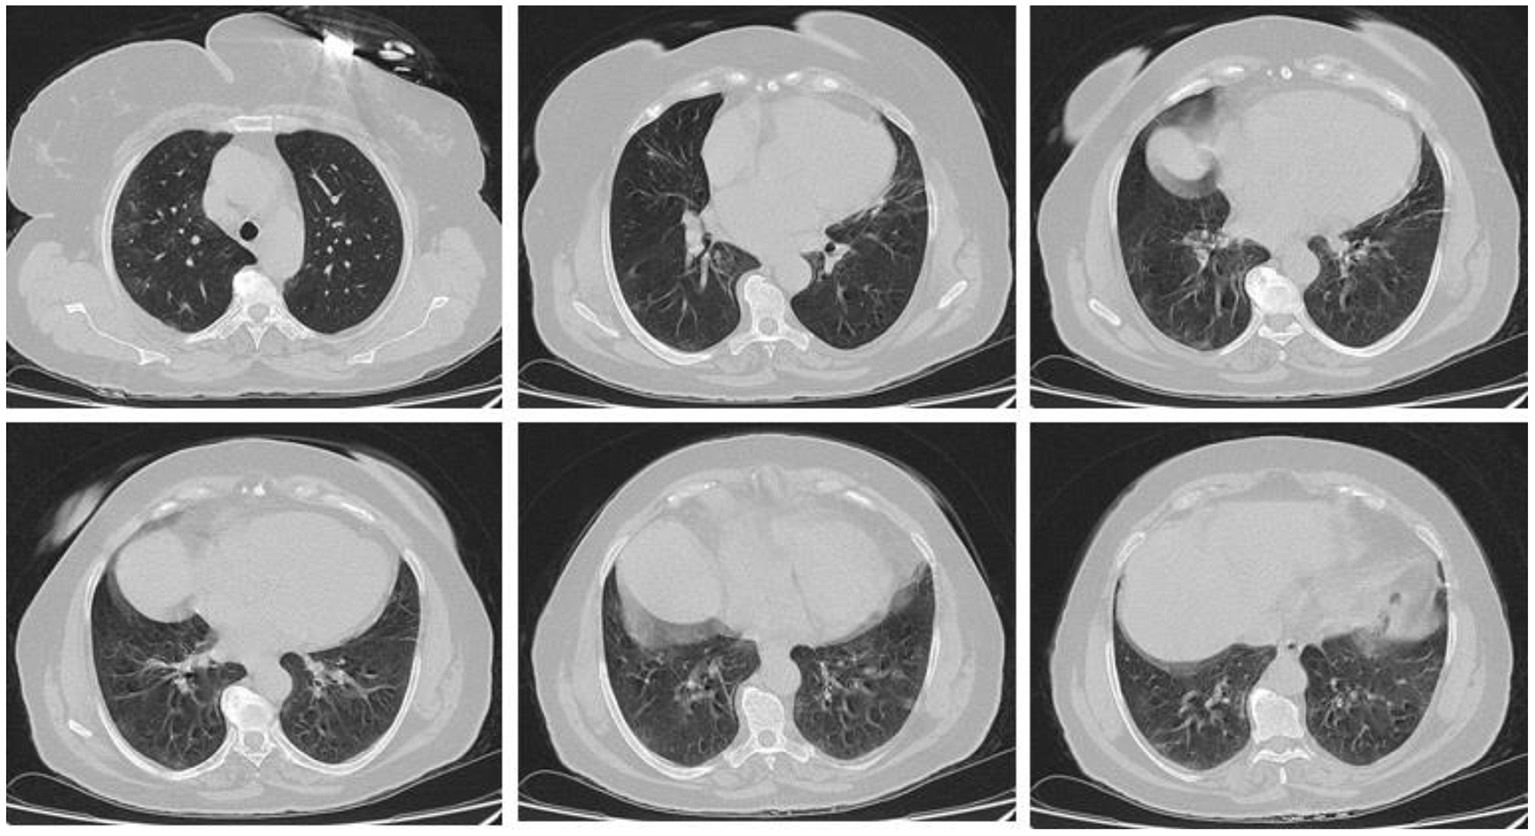

In the present study, 160 males and 70 females were enrolled to explore the association of lung CT findings in COVID-19 with patients' age, body weight, vital signs, and medical regimen. The reported major lung CT scan findings were GGO in 47 (20.4%) patients; calcified nodules in 3 (1.3%) patients; atelectasis and fibrotic band in 16 (7.0%) patients; pleural effusion and consolidation in 22 (9.6%) patients; infiltration and pneumonia in 11 (4.8%) patients; and emphysematous changes in 11 (4.8%) patients of the study sample (230 participants). Three different cases with major lung changes are shown in Figures 1–3. However, one case with minor lung CT scan findings is shown in Figure 4.

Figure 2. High resolution, axial non-enhanced spiral chest CT images (lung window) of a 59-years old patient who was confirmed to be infected by COVID-19 and admitted to hospital with Flu-like symptoms and gastrointestinal tract symptoms (mostly diarrhea). CT images show multiple faint patchy consolidations disseminated in ground-glass patterns.

Figure 3. High resolution, axial non-enhanced spiral chest CT images (lung window) of a 50-years old patient who was confirmed to be infected by COVID-19 and admitted to hospital with fever and dry cough. CT images show several airspace opacities, ground-glass shadows, and multiple sub-segmental consolidations most pronounced in the lower lobe of both lungs.